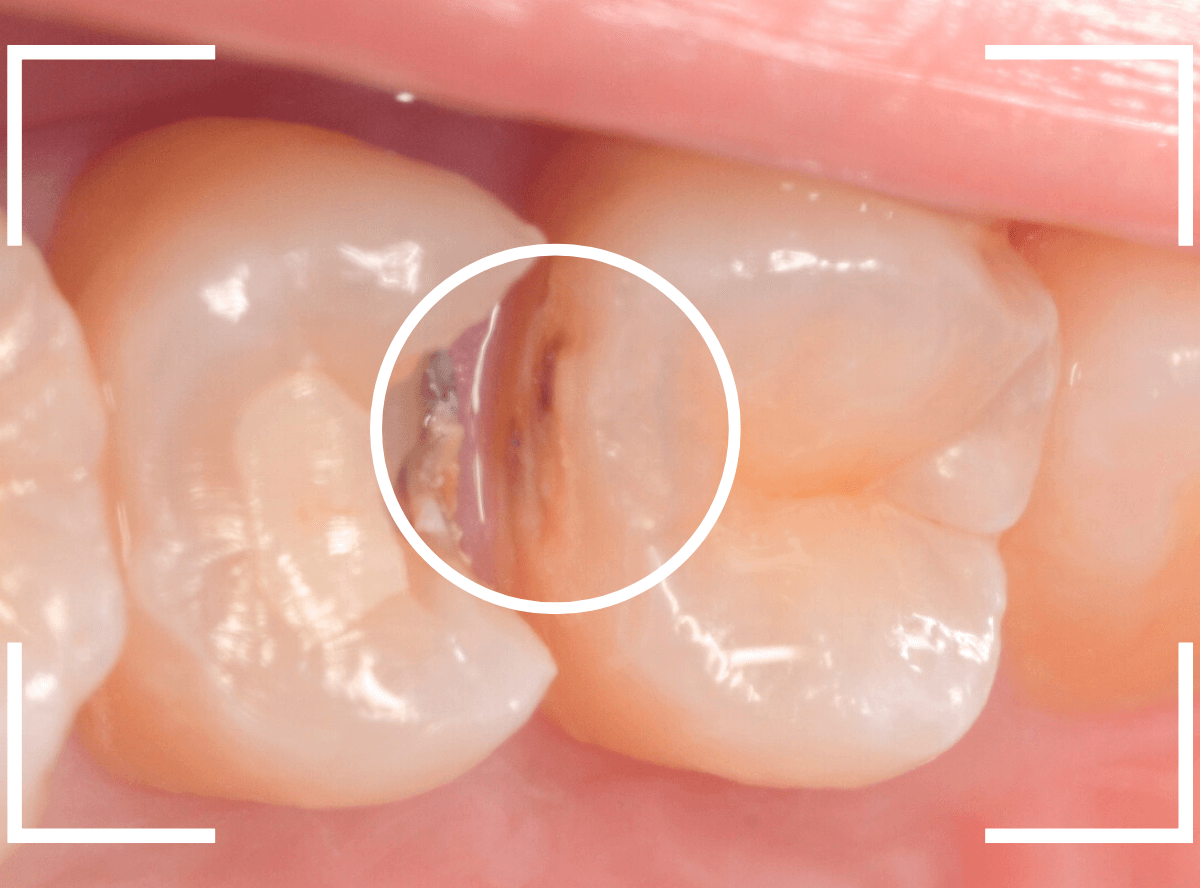

下の奥歯が虫歯になった患者さんのケースです。

〇部が虫歯の部分です。

写真で見てわかるように、常に舌が歯に触っているような状況です。

このような場合、虫歯を見つけづらいですし、治療の難易度もあがります。